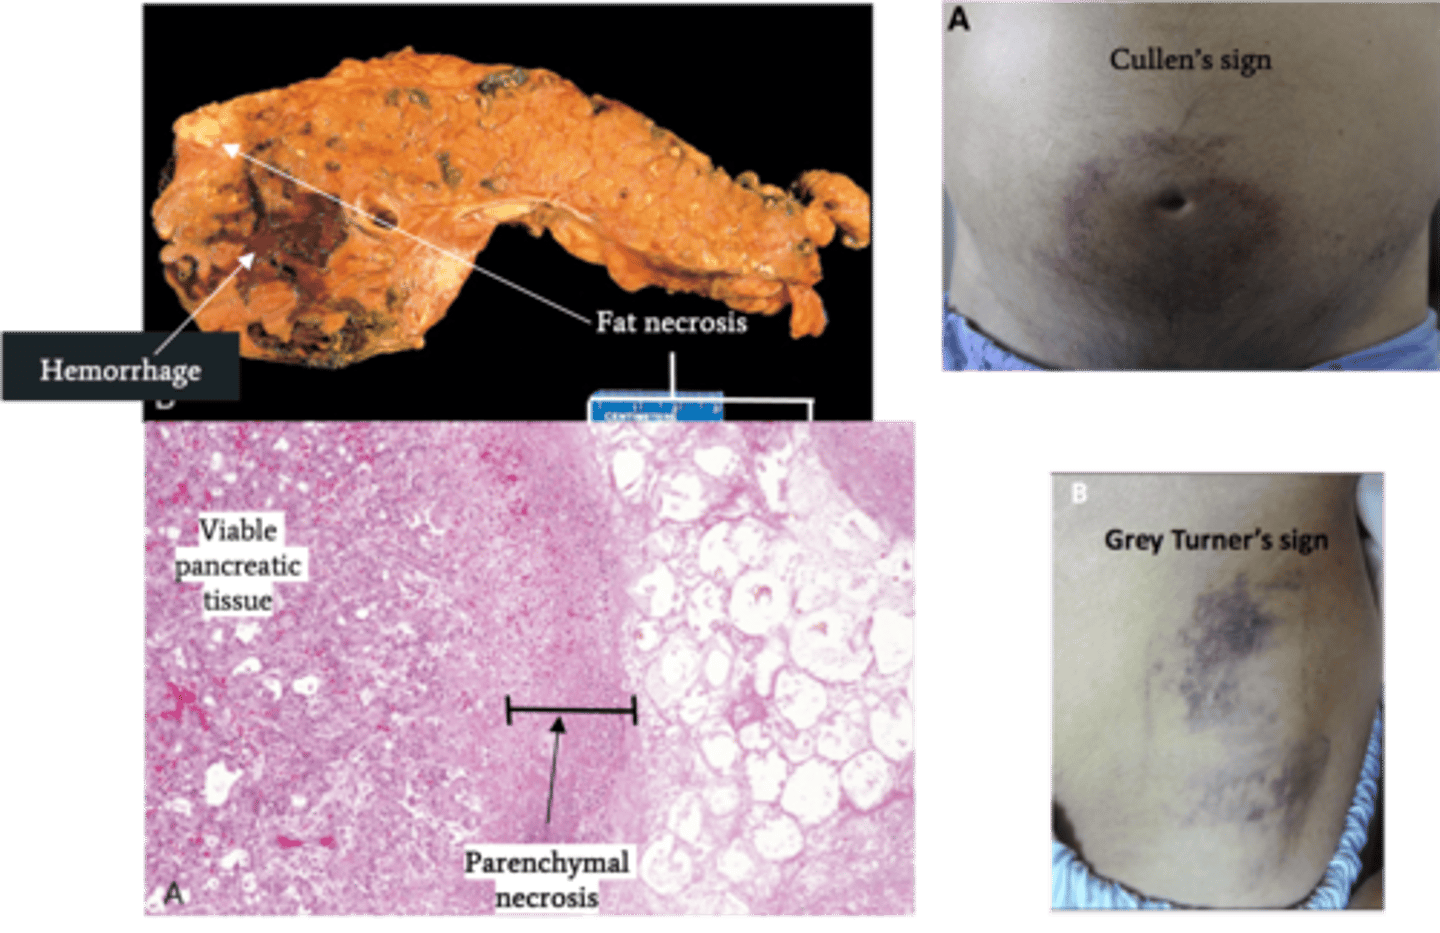

Acute Pancreatitis

Define Condition:

Acute inflammation of pancreas d/t autodigestion of pancreas by pancreatic enzymes that are prematurely activated

-Hx: ("I GET SMASHED")

> Idiopathic

> Gallstones (mostly FEMALES)

> Chronic Excessive EtOH (mostly MALES) Consumption

> Trauma

> Steroids

> Mumps

> Autoimmune

> Scorpion Sting

> Hypercalcemia/Hypertriglyceridemia

> Recent ERCP

> Drugs (Sulfa, Protease Inhibitors)

-Path:

> Alcohol:

>> Increased Pancreatic Exocrine secretion ==> PROTEIN PLUGS

>> Increased contraction of Sphincter of Oddi (prevents enzymes from leaving pancreas)

>> Induces oxidative stress in acinar cells (membrane damage)

>> May deliver proenzymes to lysosomal compartment ==> Intracellular activation of enzymes

> HyperTGs (>1000): TGs hydrolyzed into FFAs in pancreas --> Acinar cell injury

> Microvascular leakage from cytokines & Inflamm mediators ==> EDEMA/Hypovolemia --> SHOCK/Organ Fail

> Lipase ==> FAT NECROSIS

> Proteolytic destruction of pancreatic parenhcyma/blood vessels --> INTERSTITIAL HEMORRHAGE

-Sx/PE:

> Mild/Self-Limiting Epigastric Abdominal Pain

> EMERGENT = Constant, INTENSE Epigastric Pain radiating to back

>> Nausea/Vomiting

>> Skin Changes

>>> Cullen's Sign = Ecchymoses/Bruising around umbilicus

>>> Grey Turner's Sign = Ecchymosis in 1 or both flanks

-Dx:

> Labs:

>> LIPASE = MOST SENSITIVE/SPECIFIC (elevated for 8-14 days)

>> Amylase = normal by 3-5 days

>> Lipase & Amylase elevated (3x ULN) 4-12 hrs after pain

> Gross:

>> Fat Necrosis

>> Hemorrhage

> Biopsy:

>> Interstitial Edema

>> Fat Necrosis

>> Hemorrhage

>> Parenchymal Necrosis

-Tx:

-Prog:

> POOR if progresses to EMERGENT

> Acute Resp Distress Syndrome (ARDS)

> DIC (inflammation/endothelial injury --> consumption of clotting factors)

> Sepsis

> Pancreatic pseudocyst

> Hypocalcemia - POOR PROGNOSTIC FACTOR (precipitation of Ca soaps w/ fat necrosis)